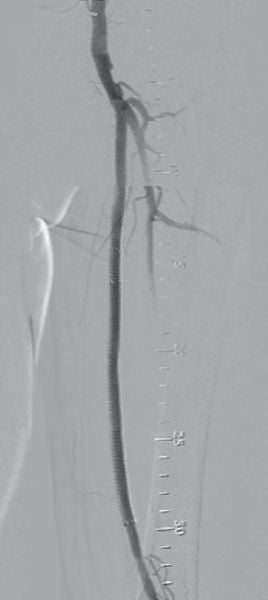

対側CFAより6 Fr 45 cm長のガイディングシースを挿入し山越えにて左EIA遠位部に進めた。この時点で圧波形は問題なかったため、手技を継続することとした。まず、5.5 Fr 100 cm長のガイディングカテーテルのバックアップ下、IVUSガイドに0.014 inchガイドワイヤー(先端荷重3 gポリマージャケットタイプ)を進めたところ、比較的容易にガイドワイヤー通過に成功した。IVUSでは全長にわたり intraplaqueを通過していたものの、血栓成分の多いプラークと考えられた。このため、5.5 FrのガイディングカテーテルをSFA遠位部に先進し、フィルターワイヤー(径 8 mm)を膝窩動脈に留置し遠位部保護を行った。続いて、5.5 Frガイディングカテーテルを用いて血栓吸引を行ったうえで、小径バルーン径 4.0 mm / 長 220 mmを使用し6 atmで前拡張した。(図3)この時点で造影にて末梢塞栓のないことを確認しフィルターワイヤーを回収、0.035 inchガイドワイヤーを用いて7 Fr 55 cm長のガイディングシースへ交換した。0.014 inchガイドワイヤー(先端荷重 1 g 親水性コートタイプ)を挿入後、SFA遠位よりバイアバーン® ステントグラフト径 7.0 mm / 長 150 mmを留置し、バルーン径 6.0 mm / 長 80 mmを用いてステントグラフト内のみ 18 atmで後拡張を行った。続いて、SFA近位部のlanding zoneをIVUSマーキングしたうえで、(図4)バイアバーン® ステントグラフト径 7.0 mm / 長 100 mmを追加留置した。先述のバルーン径 6.0 mm / 長 80 mmを用いて高圧拡張の後、近位部のみバルーン径 7.0 mm / 長 100 mmを使用し12 atmで後拡張を追加した。IVUSにてステントグラフトの拡張が良好かつmalpositionがないことを確認した。 最後に、EIAに対してベアメタルステント(BMS)径 10 mm / 長 60 mmを留置、後拡張を行って手技を終了した。(図5、6)

留置後3年までの患者フォローアップ詳細

ABI 値

左術前 0.58 → 術後 1.02 → 1Y 0.95 → 2Y 0.96 → 3Y 1.07

比較的血栓成分の多いSFAのCTO病変であり、遠位塞栓をいかに予防するかを考える必要があった。遠位塞栓の予防方法としては、フィルターデバイスの使用あるいは外部からの物理的圧迫が挙げられるが、今回は患者負担も考慮しフィルターデバイスを使用した。また、血栓吸引後の前拡張では小径バルーンを用いて、できるだけ低圧で行い、後拡張でもバイアバーン® ステントグラフト径より1 mmアンダーサイズのバルーンを使用した。また、近位端のみ同径サイズのバルーンを使用することすることにより、血栓成分を飛ばさないように配慮した。バイアバーン® ステントグラフトは理論的にはグラフト素材によるメカニカルバリア機能によって病変を押さえ込むことができると考えられるため、他デバイスに比し血栓が多く含まれる可能性のある病変でも適しているデバイスと考えられる。ほか、バイアバーン® ステントグラフトの位置決めについては、DFAならびに側副血行路を塞がないように正確に留置することが望ましいが、当院においては必ずIVUSマーキングを行って正確なデバイスの位置決めを心がけており、本症例でも正確な位置に留置することができた。本症例は、患者の職業上、運動量が多く治療前は業務に支障をきたしていたが、術後は完全に症状が消失し業務遂行が可能になったとのことであった。現在、 外来にて3年フォローが完了しているが、良好な経過を維持できている。